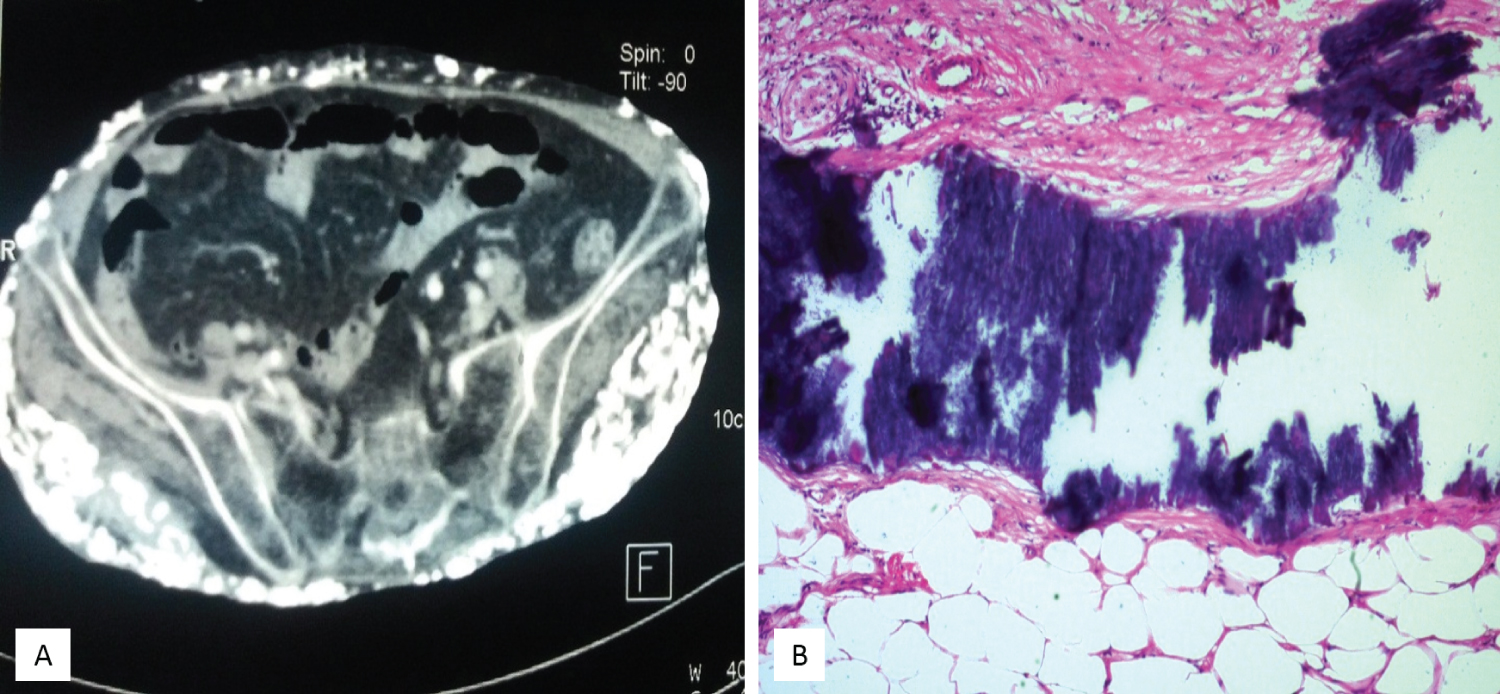

The laboratory data showed normal serum calcium, phosphorus, parathyroid hormone, and muscle enzyme levels. A plain film X-ray showed numerous small soft tissue calcifications extensively scattered over her pelvic region (Figure 2A), thigh, knee, and lower leg (Figure 2B). However, computed tomography revealed that the calcified lesions were only present in the skin and subcutaneous tissues, with no muscle, vessel, or visceral organ invasion (Figure 3A). Pathology of the skin and subcutaneous tissue showed multiple calcified nodular formations and moderate dermal lymphocyte infiltration (Figure 3B). The diagnosis was extensive calcinosis cutis universalis. The patient received bisphosphate 10 mg/kg/day for 6 months and diltiazem 30 mg/day for more than 1 year, and intralesional corticosteroids. However, the general condition still progressed.

Figure 3: (A) Computed tomography shows calcifications involving the subcutaneous fat space and respecting the muscle planes and fascias; (B) Pathology of the skin and subcutaneous tissue reveal patches of black-colored staining, indicating tissue calcification.